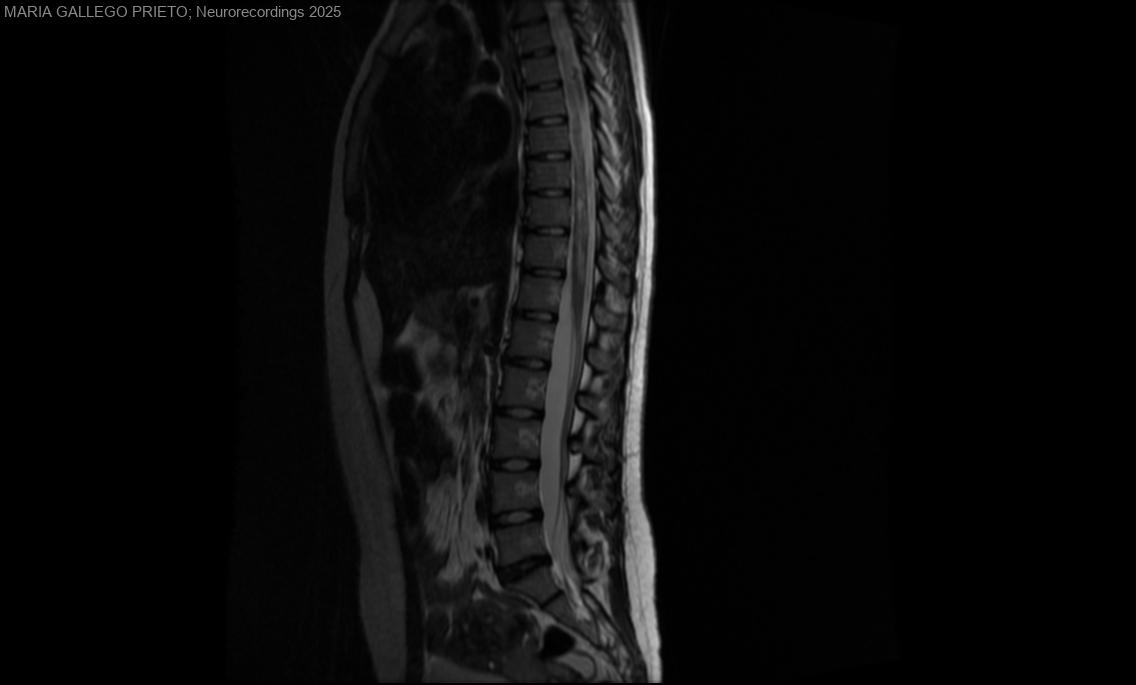

Mielopatía cervico-dorsal secundaria a enfermedad del espectro de la neuromielitis óptica (TENMO)

Diagnóstico final: Mielitis extensa (cervical y dorsal) secundaria al Trastorno del espectro de la Neuromielitis Óptica (TENMO)

Mujer de 18 años, sin antecedentes de interés, que acude a Urgencias por parestesias de 2 meses de evolución: inicialmente en ESD, posteriomente en hemitórax, hemiabdomen derecho, ambas EEII y ESIzq. Además torpeza en manos desde hace 2 semanas, sensación...